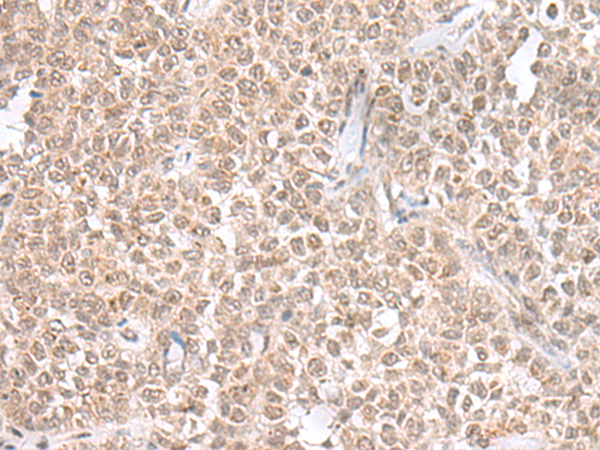

分类: 科研抗体货号: P09794别名: HK2应用: WB,IHC反应种属: Human, Mouse